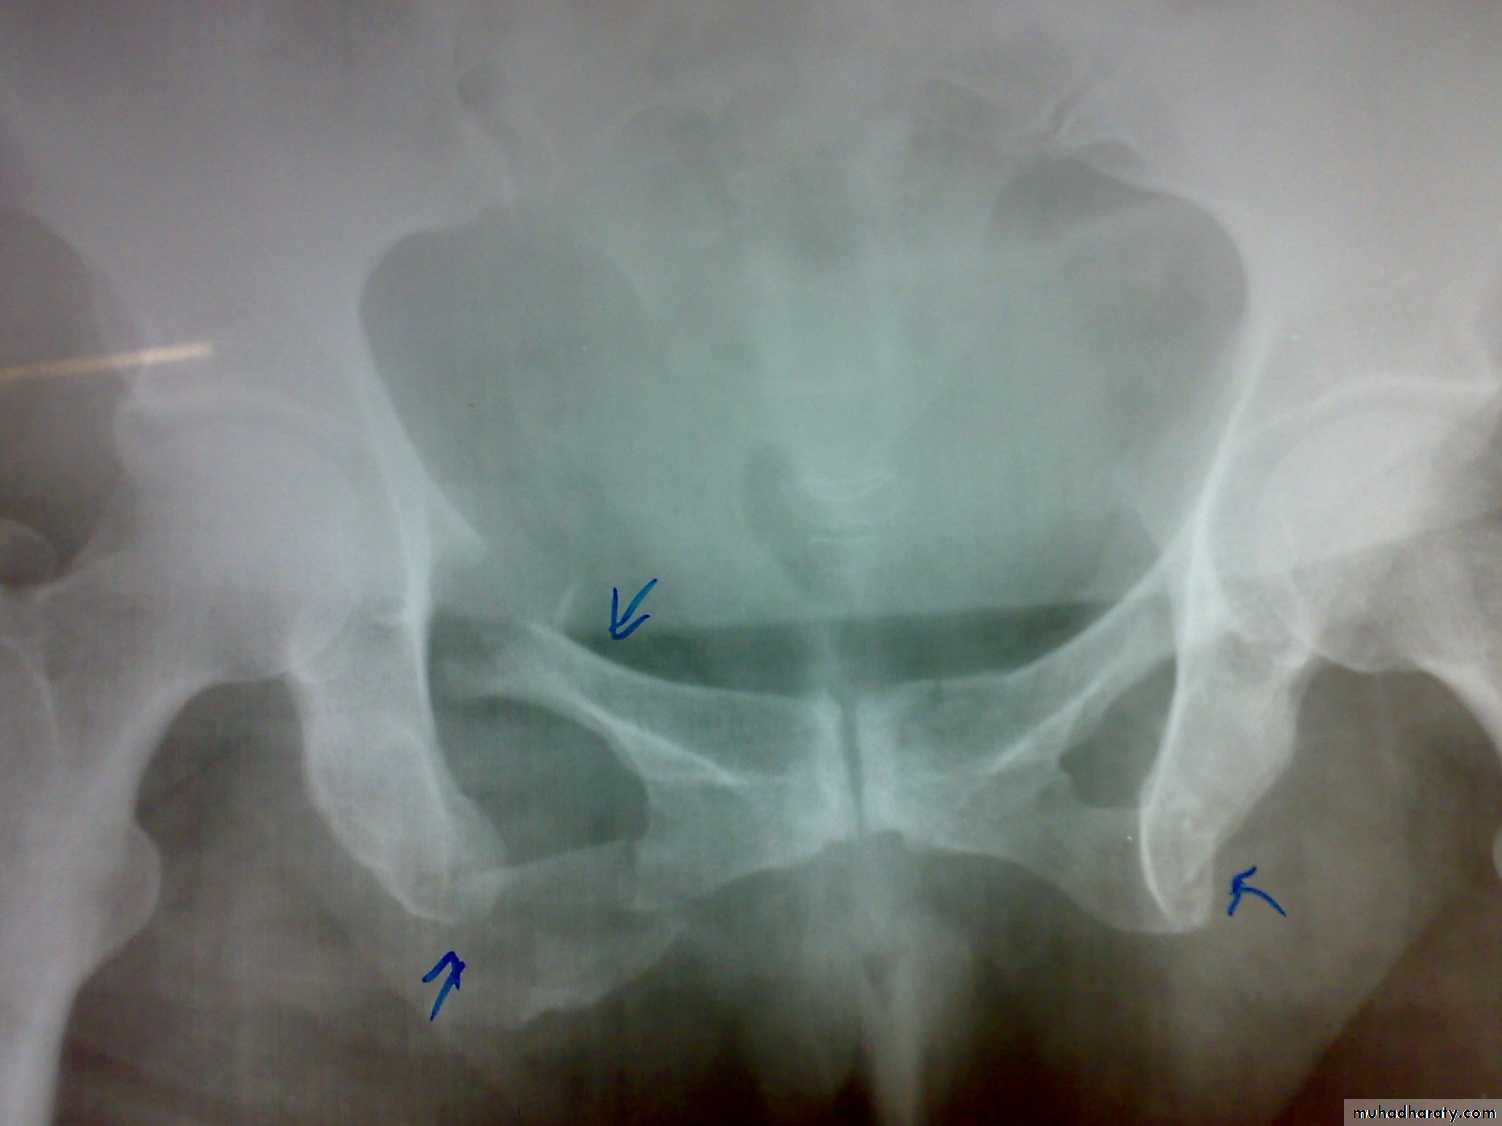

1- antero-posterior compression (open book).

X- ray: Ideally five views should be obtained : Standard anteroposterior view, inlet view, outlet view, right oblique view, and left oblique view, but x-ray shouldn't be done until the patient become stable .

Treatment of the fracture

Open book injuries with a gap of less than 2cm at the symphisis pubis can be treated with bed rest for 6 weeks. If the gap is more than 2cm, external fixator with pins in the iliac blades and anterior bar may be used for 8-12 weeks. The other option is anterior plating.Severe vertical shear and compression injuries are the most dangerous and most difficult to treat. The fracture or dislocation must be stabilized by external fixation or posterior iliosacral screw or anterior plating with posterior iliosacral screw . Vertical force fractures may be treated by open reduction and internal fixation or skeletal traction and non weight bearing for 3 months